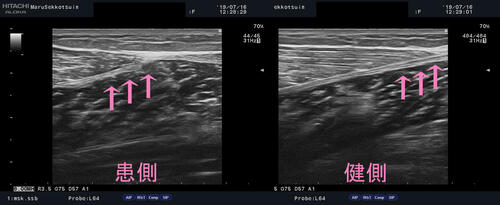

問診後、しっかり視診、触診を行ったところ、腓腹筋内側部 筋腱移行部に圧痛、腫脹を触知。

深さ、損傷範囲を調べる為にエコー検査。

確認したところ「腓腹筋内側部 筋腱移行部の肉ばなれ」でございました。